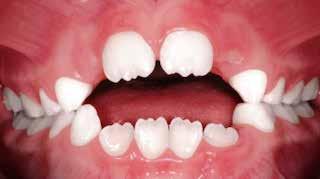

Presentazione del caso > F.V, bambino di cinque anni, presenta una malocclusione di II Classe scheletrica, III Classe dentale molare e canina destra e sinistra, morso inverso anteriore. Le arcate dentali mostrano usura degli elementi dentari anteriori a causa dell’occlusione patologica. Le linee mediane, superiore ed inferiore, sono centrate; il frenulo labiale superiore patologico per un’eccessiva estensione inter-incisale.

Il piano di trattamento prevede l’utilizzo di un dispositivo elastodontico di III Classe, da portare per due ore diurne e tutte le notti in modo passivo, senza effettuare alcun esercizio, al fine di ripristinare una relazione molare e canina bilaterale di I Classe ed il corretto avanzamento maxillare e inibire l’eccessiva crescita mandibolare. È possibile ottenere il risultato in pochissimi mesi di terapia, essendo la crescita del paziente molto attiva.

Dall’esame clinico si evince la III Classe dentale, l’inversione anteriore e l’over-jet negativo.

Una volta ottenuta la correzione del rapporto molare ed incisale, l’apparecchio elastodontico verrà portato dal paziente solo durante la notte per stabilizzare il risultato ottenuto e guidare l’eruzione degli elementi dentari per un totale di quattordici mesi di terapia. ad inizio trattamento :

Considerazioni > L’analisi cefalometrica ad inizio trattamento dimostra la II Classe scheletrica con protrusione del mascellare superiore e prognazia mandibolare; tendenza alla crescita verticale. L’esame clinico evidenzia una protrusione mandibolare funzionale.